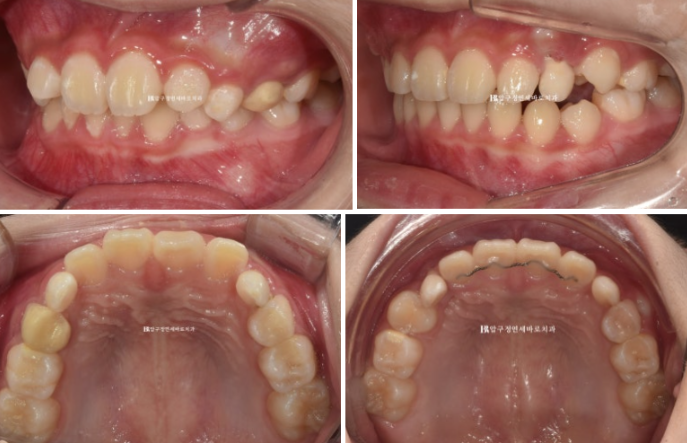

장치를 열심히 착용했고 2022년 9월부터 2023년 5월까지 변화 모습입니다.

2022.09~2023.05

이렇게 가지런해진 앞니에 철사유지장치까지 붙여놓고 잠시 송곳니 맹출을 기다리는 휴지기 즉 쉬는 시간을 가졌습니다.

휴지기에는 마지막 꼈던 장치를 잘때만 끼면서 편하게 지내게 됩니다.

그 이후 3개월 간격으로 정기검진을 하던 중 송곳니가 나오기 시작했는데 송곳니 날 공간이 약간 좁은 것이 관찰되었습니다.

송곳니가 충분히 나오면 재제작을 하기로 하고 의도적으로 더 기다려서 7개월 후인 24년 1월 재제작을 시작했습니다.

재제작에 들어갔고 24년 7월까지, 6개월간 한 세트의 추가장치를 더 꼈습니다.

2022.09~2024.09